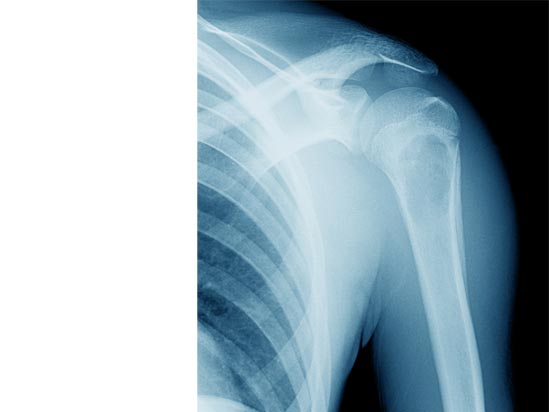

THE SKELETAL STRUCTURE, MUSIC SCHOOL IN BERRIOZAR